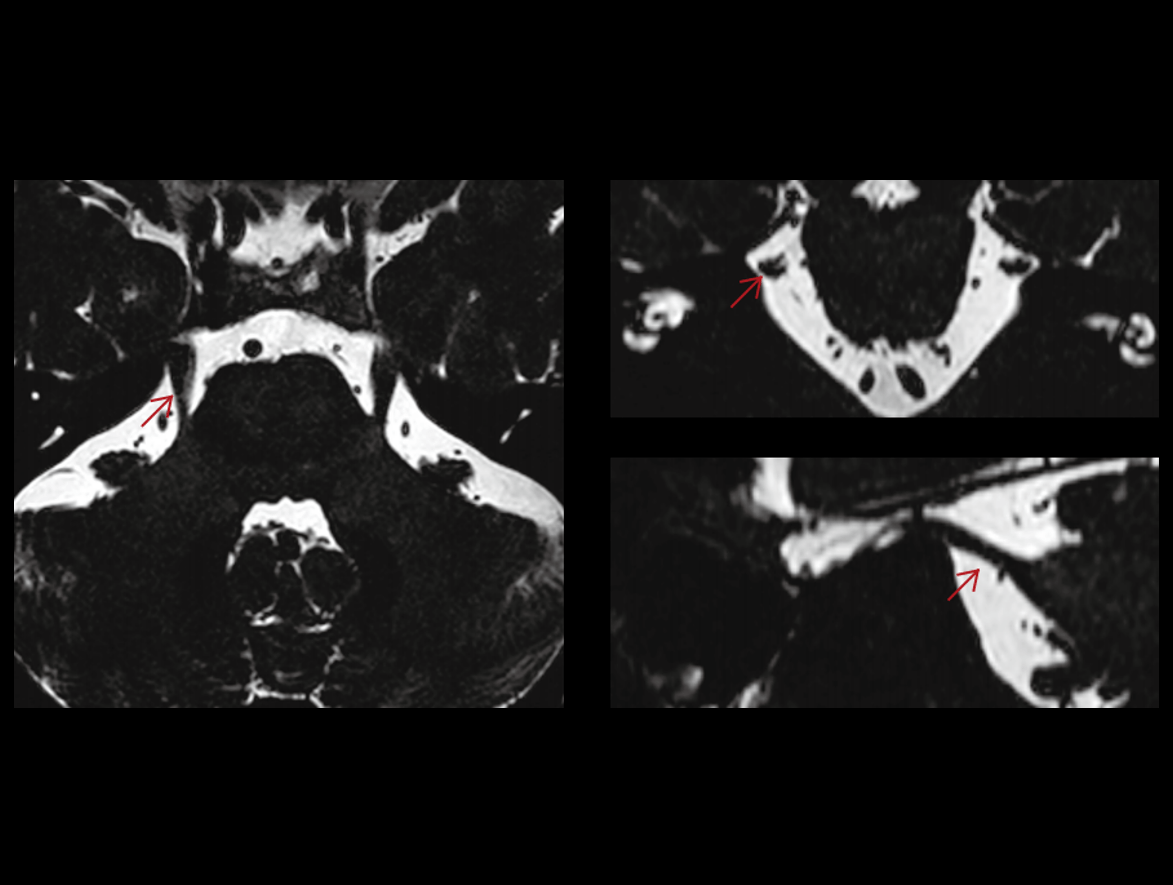

Nerv trigemen

TMJ